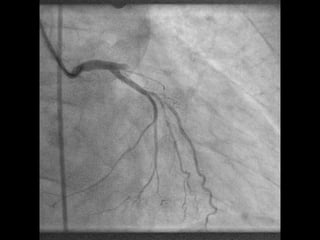

Vorhofflimmern und

koronare Stentimplantation

Individualisierte antithrombotische Therapie

„Triple“-Therapie bei Patienten mit

Vorhofflimmern und akuter/elektiver

Stentimplantation

• 8-10% von Vhfli-Patienten bekommen ein

ACS oder benötigen eine elektive

• 15-20% nach ACS oder elektiver

Stentimplantation entwickeln Vhfli